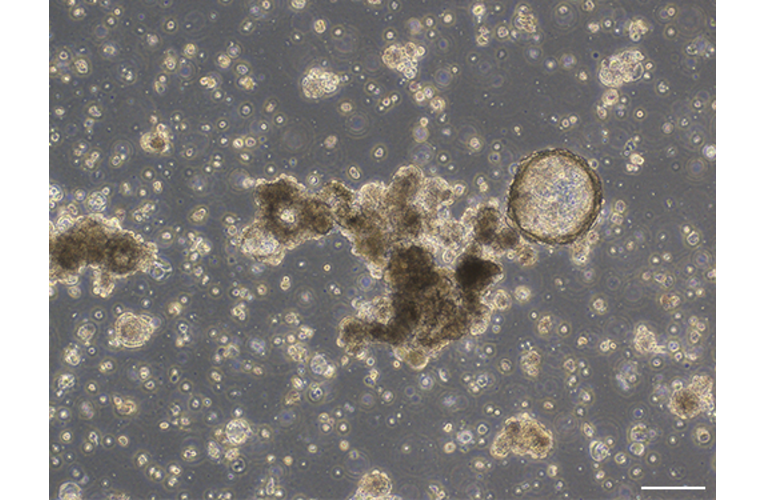

- Tool name: REME030 Uterine corpus cancer organoid

- Tool sub-type: Organoids

- Description: A series of novel patient-derived organoids (PDOs) have been constructed from different tumor tissue types under the Fukushima Translational Research Project, designated as F-PDO. F-PDOs form large cell clusters with a morphology similar to the original tumor and can be cultured for more than six months. Our comparative histological and comprehensive gene expression analyses have shown that the characteristics of F-PDOs were similar to their source tumors, even after long-term growth in culture conditions